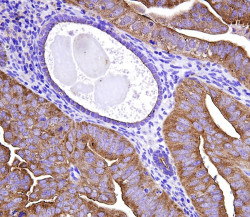

Un equipo internacional de investigadores del Centro de Investigación Hospitalaria de la Universidad de Montreal (CRCHUM), el Programa de Investigación Militar sobre el VIH de los Estados Unidos y el Centro de Investigación sobre el SIDA de la Cruz Roja Tailandesa ha demostrado que los primeros reservorios de VIH establecidos siguen siendo "sensibles" durante estas etapas tempranas y podrían reducirse unas 100 veces al iniciarse inmediatamente el tratamiento antirretroviral.